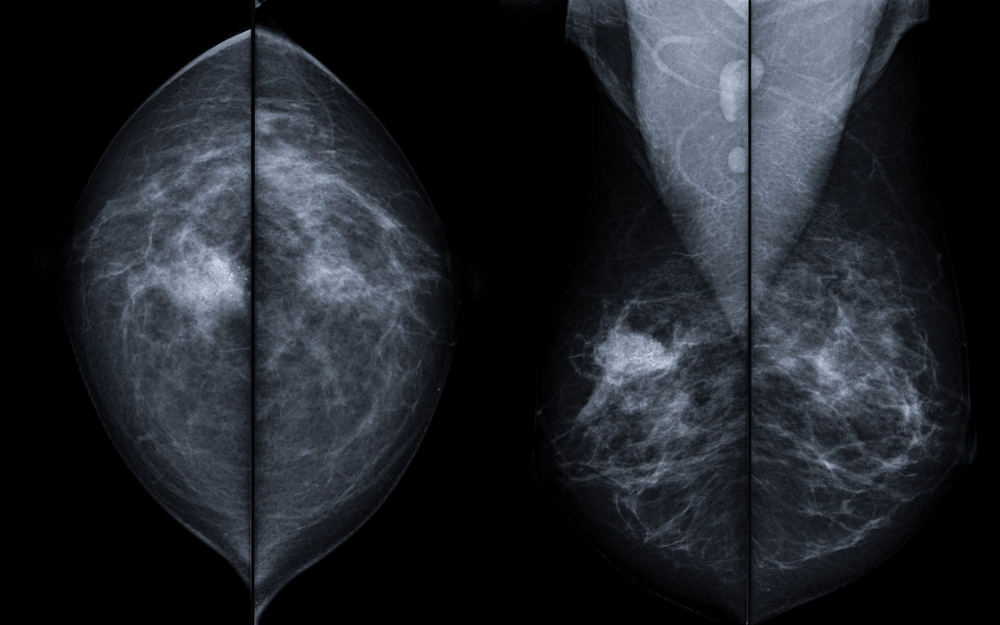

In this Healthed lecture, Dr Sally Meade provides a refresher on assessing and managing breast lumps, including an update on the most appropriate investigations, imaging and likely diagnosis. She will also be giving an overview of the latest thinking and recommendations for other breast presentations including breast pain and nipple discharge.